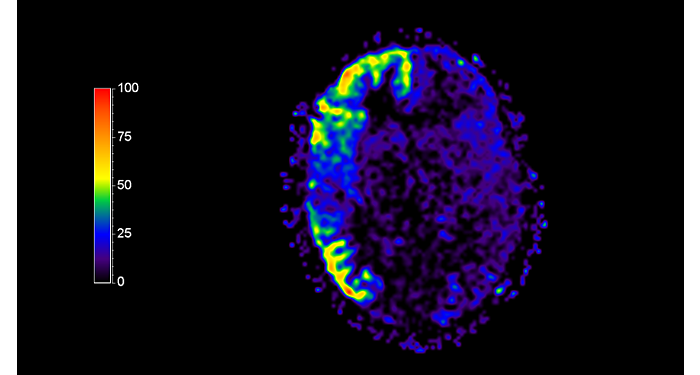

70% of radiologists consider neuro indications to be challenging, mostly due to a lack of appropriate imaging and visualization techniques¹. Philips aims to provide the best possible diagnostic clarity and treatment guidance for all patients with neurological disorders. By leveraging our dStream digital platform, this year, we are introducing, a set of novel imaging and visualization strategies. These may empower you to resolve complex neuro questions with more certainty, as well as unlock new neuro territories in advanced Neurofunctional applications. This is a key step towards elevating neuro diagnostics and ultimately touching more lives with MR imaging. ¹ TMTG Market Survey 2016

New neuro applications